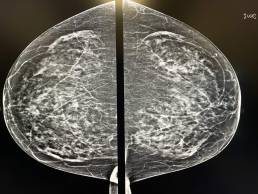

Femme de 67 ans, mammographie de dépistage.

MammoScreen™ pointe un foyer de microcalcification irrégulière, polymorphe (red flag) externe du sein gauche.

L’échographie retrouve une formation ovalaire à l’union des quadrants externes du sein gauche contenant des microcalcifications.